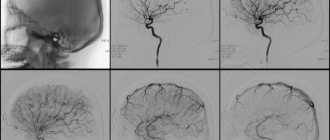

Из инструментальных методов диагностики большую роль играет УЗИ артерий. Наиболее информативным методом диагностики синдрома Лериша является ангиография — введение рентгенконтрастного вещества в аорту с последующими сериями рентгеновских снимков.